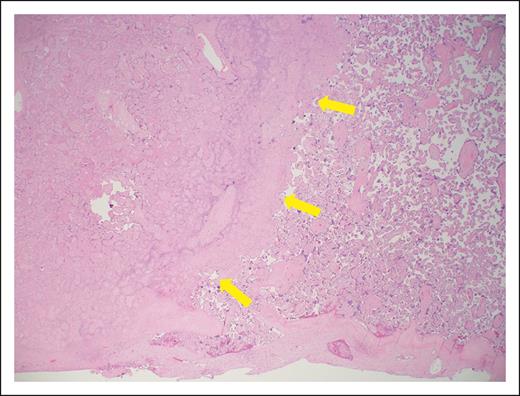

On hospital day 3, worsening features of HELLP syndrome (Table 2) and worsening fetal umbilical artery Doppler assessments required delivery. Following delivery, maternal blood pressure was adequately controlled with oral labetalol, and therapeutic LMWH was restarted 24 hours after cesarean delivery. Maternal laboratory parameters returned to normal by postoperative day 4. Placental histopathologic examination found widespread villous infarction indicative of maternal malperfusion10 (Figure 1). The small-for-gestational age neonate had a hospital course complicated by multiple medical comorbidities, requiring a hospital stay of 62 days.

Photomicrograph of placental section (hematoxylin and eosin, low power). The maternal surface is at the bottom. There is villous infarction on the left (yellow arrows), and accelerated villous maturation seen on the right. These findings are indicative of vascular malperfusion, as described in APS pregnancy.10